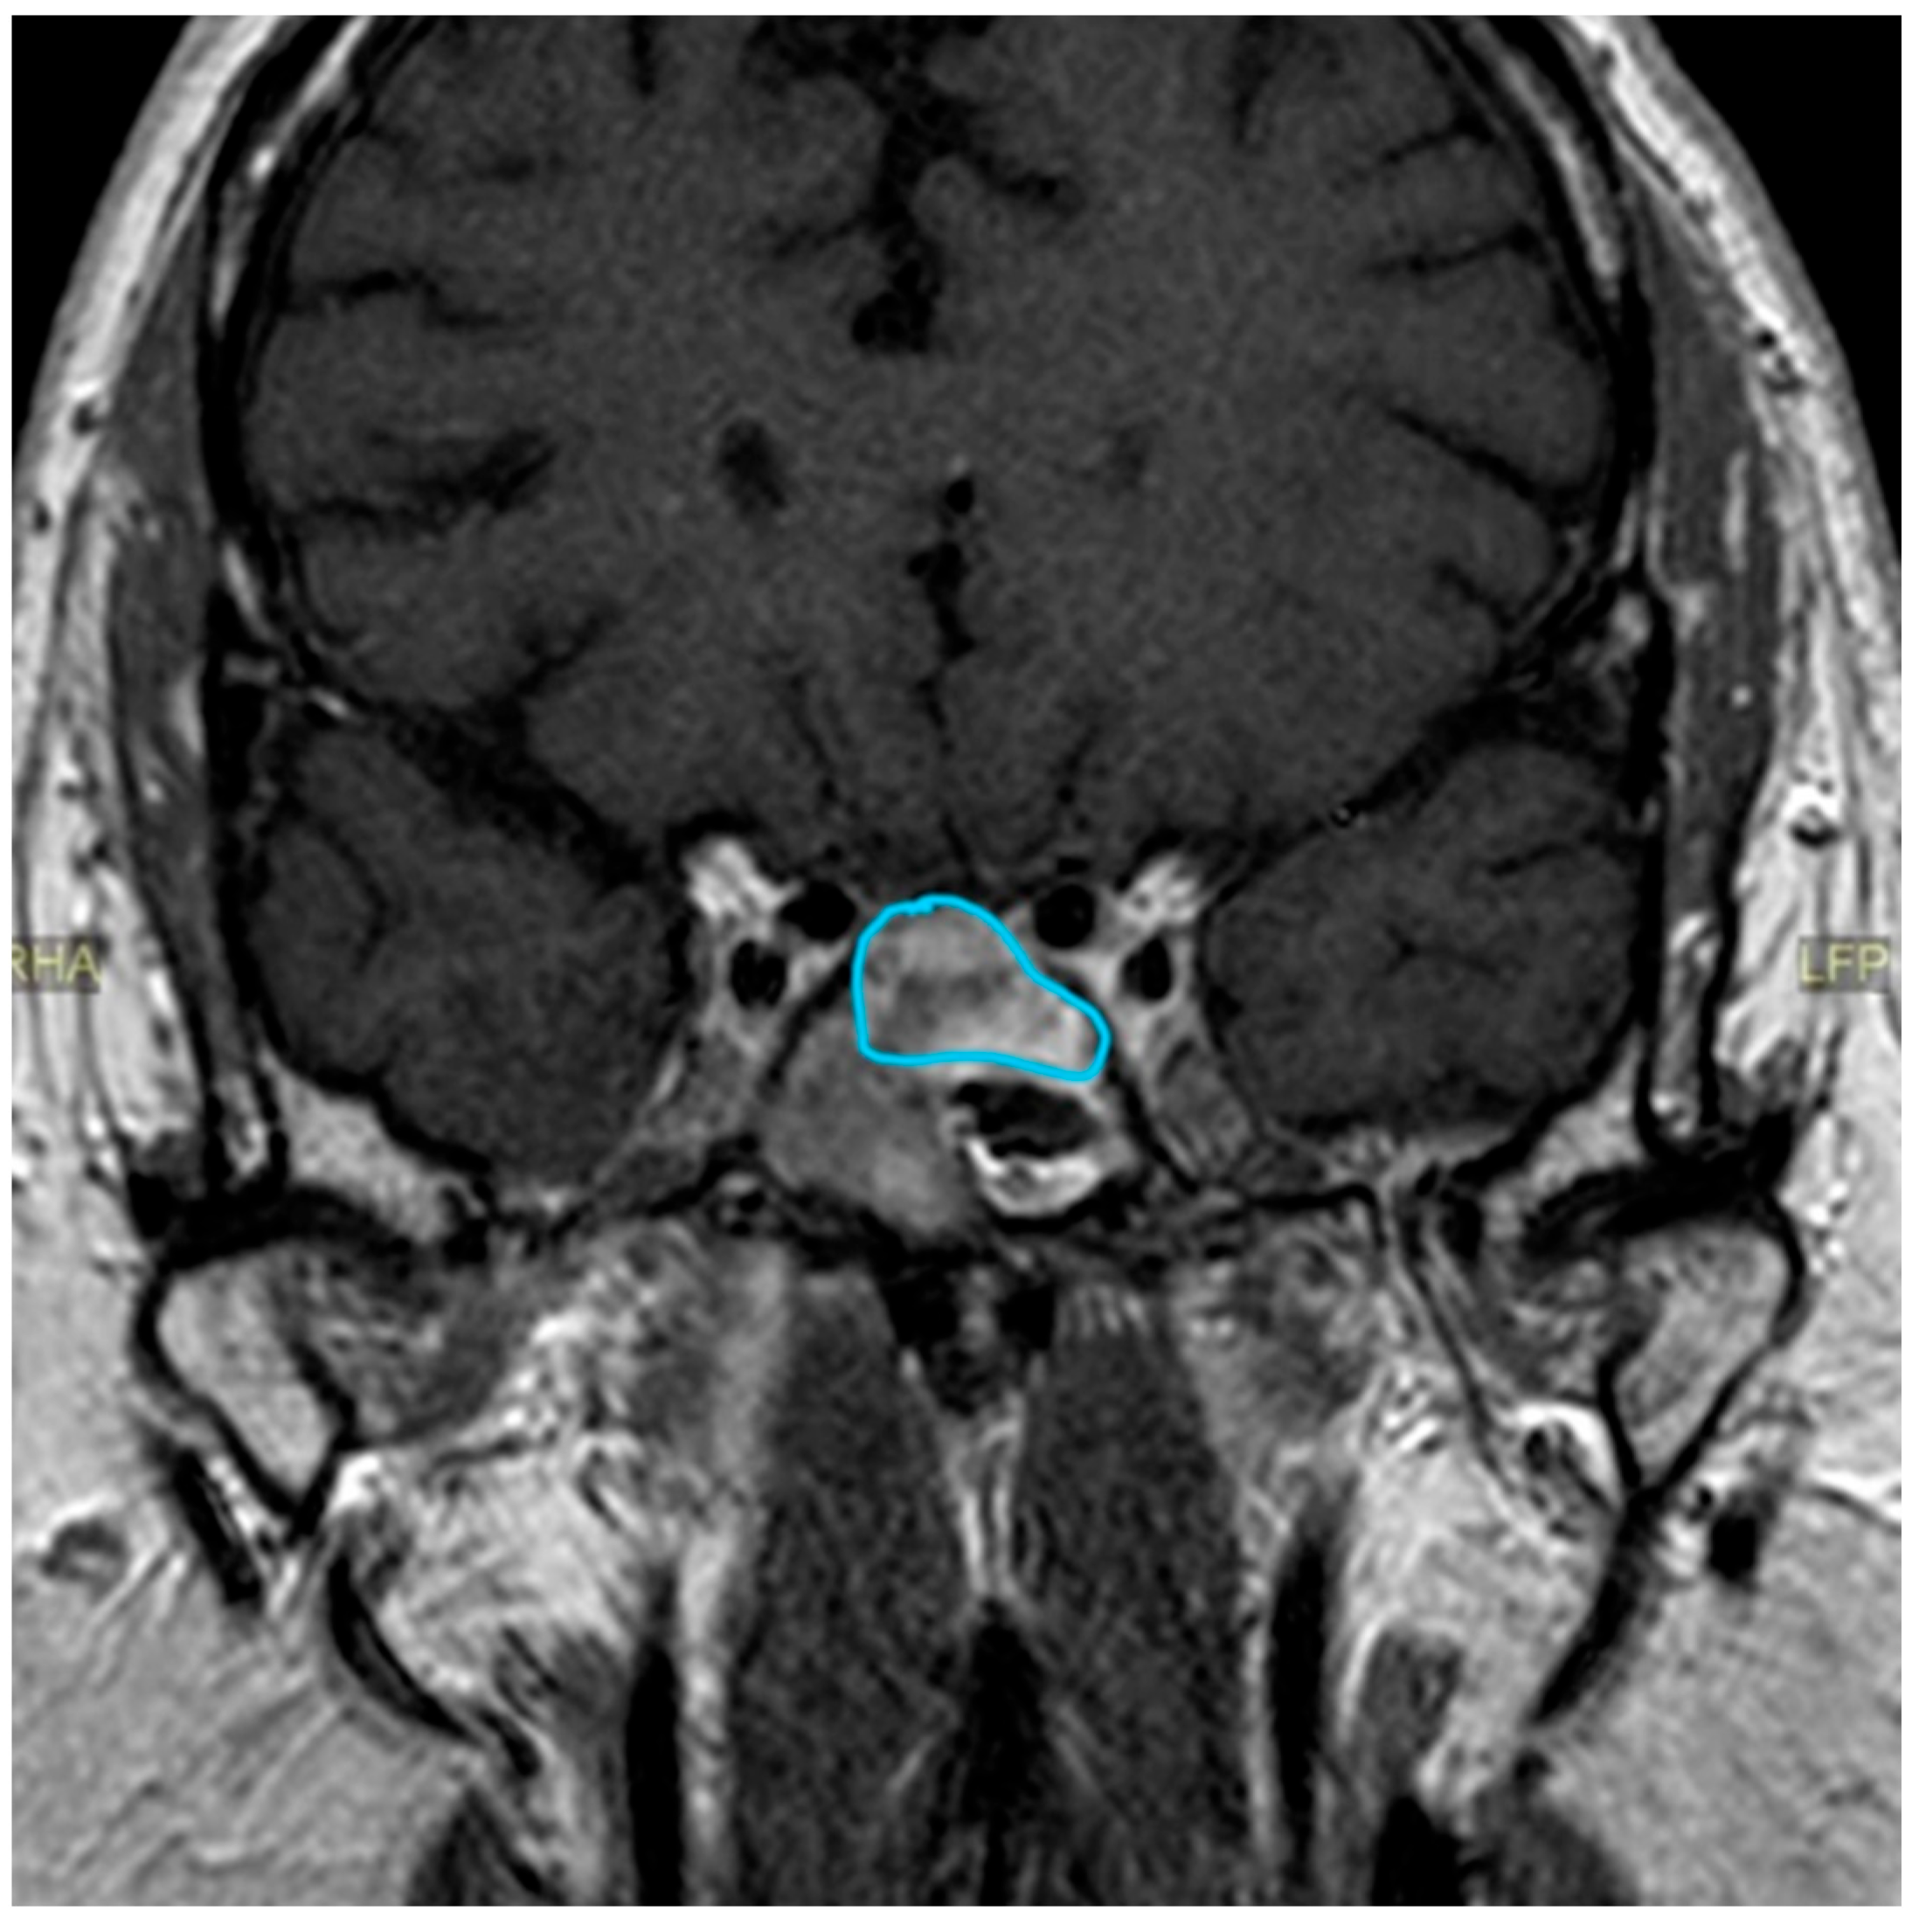

| Date | July 2018 | January 2019 | July 2019 | June 2020 | October 2020 | December 2020 | June 2021 |

|---|---|---|---|---|---|---|---|

| Prolactin (ng/mL) | 22.1 | 27.6 | 71.2 | 681.9 | 0.4 | 1.8 | |

| MRI | Macroadenoma (20 × 20 × 18 mm) with signs of pituitary apoplexy. Invasion of the optic chiasm, hypothalamus, and the left cavernous sinus. | 5 × 2 mm nodular structure that could be related to remnant glandular tissue. Persistent left deviation of the pituitary stalk. | Tumor growth (16 × 14 × 11 mm). Significant compression of the optic nerve and the optic chiasm. | Discrete decrease in volume of the tumor (13 × 12 × 8 mm). No compression of the optic nerve and the chiasm. | Volume reduction (13 × 10 × 6 mm). The structure is no longer in contact with the gyrus rectus and the subcallosal area. | ||

| Treatment | First surgical procedure | Second surgical procedure | Cabergoline started |